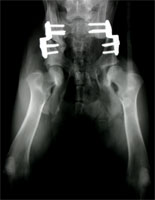

Sechs Wochen postoperativ wird der Hund erneut einer Lahmheitsuntersuchung unterzogen und das Fortschreiten der knöchernen Fusion durch eine Röntgenuntersuchung in tiefer Sedation beurteilt. Gegebenenfalls wird zu diesem Zeitpunkt die zweite Seite operiert (Abb 15). Es zeigt sich in der Regel eine deutliche Kallusbildung an der Osteotomiestelle des Os ilium. Die Manipulation der Articulatio coxae sollte einen guten Grad von Beweglichkeit ergeben. In den besonderen Fällen, bei denen eine 40°-Platte eingesetzt wurde, kann die Abduktion und Extension des Hüftgelenkes ein wenig eingeschränkt sein. Ab Woche 6 sollte mit einem aktiven aufbauenden Bewegungstraining begonnen werden. Auf den besonderen Wert eine Physiotherapie braucht nicht hingewiesen zu werden.

DBO Kontrollröntgen nach 6 Monaten

Abbildung 15: Kontrolle nach 6 Wochen zeigt die Fusion des Os ilium auf der linken Bildseite. Die zweite Seite ist frisch umgestellt.

In Studien, die sich über einen Zeitraum von 8 Jahren erstreckten, zeigten 76 % der DBO-Operierten noch ein exzellentes Ergebnis ohne Coxarthrose mit uneingeschränkter Beweglichkeit und völliger Schmerzfreiheit (Abb. 16). Bei dem Rest der Patienten zeigten sich röntgenologisch leichte Arthroseerscheinungen, die klinisch jedoch zu keiner Einschränkung der Bewegung führten und in der Regel auch keine Gabe von Schmerzmitteln erforderten.

DBO bilateral Ausheilungsergebnis

Abbildung 17: Ausheilungsergebnis einer bilateralen Dreifachen Beckenosteotomie. Die bisweilen ausbleibende Fusion des Os ischium ist klinisch bedeutungslos.

Fazit

Die Dreifache Beckenosteotomie (DBO) beseitigt nicht nur die Lockerheit des dysplastischen Hüftgelenkes sondern führt zu einem festen und tiefen Sitz des Caput ossis femoris im Acetabulum. Die tragende und belastete Gelenkfläche wird durch die Umstellung verdreifacht bis vervierfacht. Dies führt den Stress auf den Gelenkknorpel in physiologische Dimensionen zurück. Im Idealfall sind im weiteren Verlauf keinerlei röntgenologische Anzeichen einer Coxarthrose zu verzeichnen (Abb. 17). Treten sie bei operierten Patienten mit schwersten HD Graden später dennoch auf, so sind sie von der Form her milde und von keiner Lahmheitssymptomatik begleitet. 92 % der Patienten sind nach spätestens 7 Monaten völlig lahmheitsfrei. Langzeitstudien beweisen, dass die Hunde im Laufe ihres Lebens klinisch fast immer beschwerdefrei sind und selbst im Alter weder antiphlogistische Medikamente noch neuerlicher chirurgischer Interventionen bedürfen. Es wäre wünschenswert, wenn die Tierbesitzer dysplastischer Junghunde mehr über die Chancen und Möglichkeiten informiert würden, die die Dreifache Beckenosteotomie eröffnet. Sie ist bei korrekter Indikationsstellung sowie Erfahrung der Operateure der Goldstandard in der Therapie der juvenilen Hüftgelenksdysplasie und ein Jahrzehnte lang international erprobtes und bewährtes Verfahren.